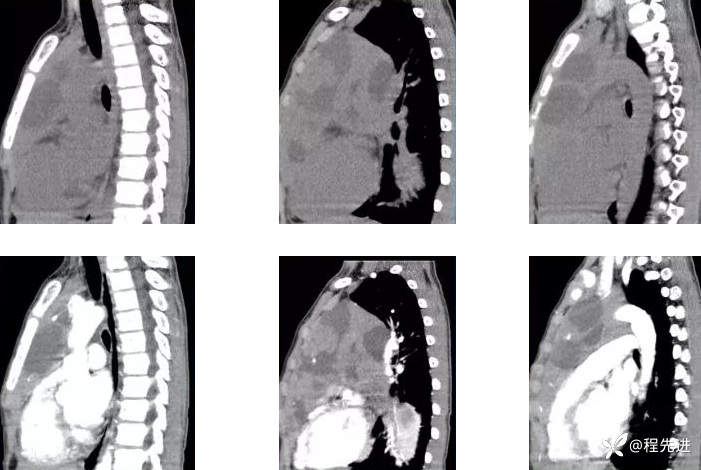

矢状位重建,上平扫,下增强